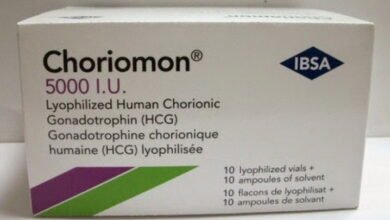

كل المعلومات عن حقن كوريونيك جونادوتروفين Chorionic Gonadotropin والسعر

حقن كوريونيك جونادوتروفين هي حقن الغدد التناسلية المشيمية هي حقن تعمل على إنتاج هرمون يسمى HCG، والذي يتم استخلاصه من…